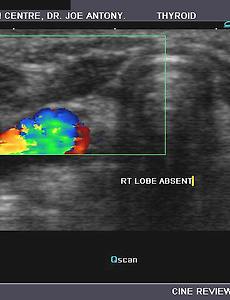

Agenesis of the thyroid Agenesis of the thyroidAgenesis of the thyroidAgenesis of the thyroid Sonography of the thyroid in this 1 yr. old female child revealed congenital absence of the entire thyroid. Note the empty fossae where the right and left lobes would normally lie. The carotid artery and jugular vein of both sides are seen in the color doppler images. These ultrasound and color doppler images suggest congenita.. 2009. 9. 14. 이전 1 2 다음